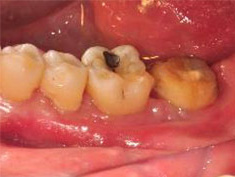

#37進行骨移植併用引導組織再生手術。

術後一年之全口X光片, #37近心側可見明顯骨充填與放射線密度增加。 牙周再生手術完成一年後追蹤,全口牙齦發炎狀況改善,牙周組織呈現健康狀況。#37金屬燒附陶瓷牙冠製作完成。